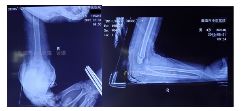

复位固定后拍片情况如下:

治疗一个月后复查情况如下: